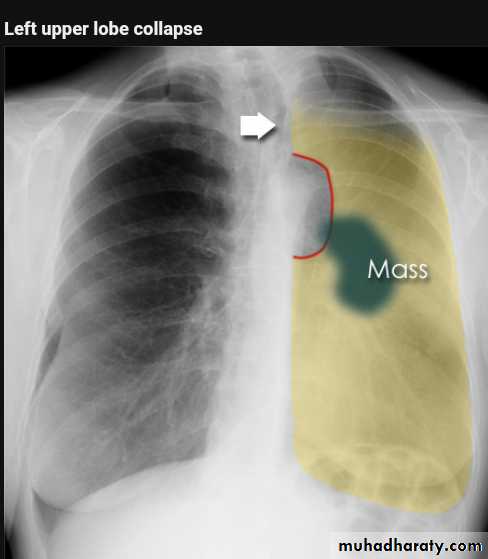

Left upper lobe collapse has distinctive features but can be challenging to identify on chest radiographs by the uninitiated.

Radiographic features

The left upper lobe collapses anteriorly becoming a thin sheet of tissue apposed to the anterior chest wall, and appears as a hazy or veiling opacity extending out from the hilum and fading out inferiorly . It thus reverses the normal slight increase in radiographic density seen as you move down the lung (due to increased thickness of the chest soft tissues).

Parts of the normal cardiomediastinal contour may also be obliterated where the left upper lobe, particularly the lingula abut the left heart border. The anterior parts of the aortic arch are also often obliterated from view.

In some cases the hyperexpanded superior segment of the left lower lobe insinuates itself between the left upper lobe and the superior mediastinum, sharply silhouetting the aortic arch and resulting in a lucency medially. This is known as the HYPERLINK "http://radiopaedia.org/articles/luftsichel-sign" luftsichel sign.

The left hilum is also drawn upwards, resulting in an almost horizontal course of the left main bronchus and vertical course of the left lower lobe bronchus.

Non-specific signs indicating left sided atelectasis will also be present, including:

elevation of the hemidiaphragm

'peaked' or 'tented' hemidiaphragm: HYPERLINK "http://radiopaedia.org/articles/juxtaphrenic-peak-sign" juxtaphrenic peak sign

crowding of the left sided ribs

shift of the mediastinum to the left

On lateral projections the left lower lobe is hyperexpanded and the oblique fissure displaced anteriorly. There is associated increase in the retrosternal opacity.